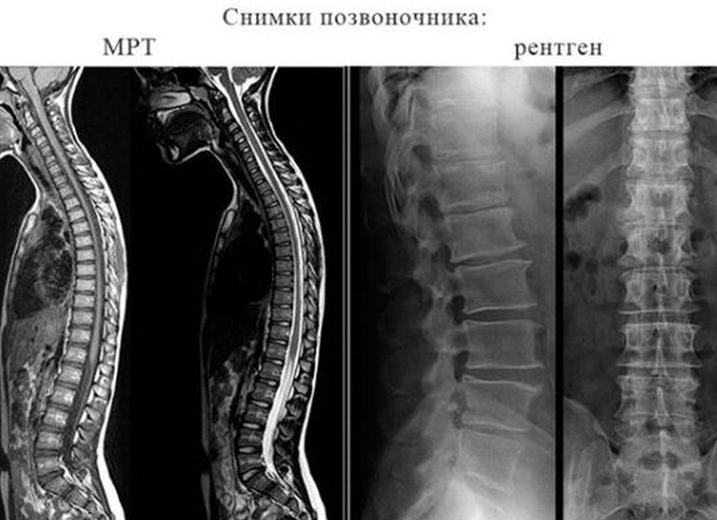

Что лучше рентген или мрт поясничного отдела позвоночника

Что лучше рентген или мрт позвоночника

Рентген позвоночника в большинстве случаев назначают, чтобы установить верный диагноз. Рентгенография спины не нуждается в какой-либо специальной подготовке больного. Наиболее полные сведения о возможных патологиях позвоночника получаются путем просвечивания позвоночного столба. Просвечивание делают в двух проекциях: больной лежит на спине – прямой снимок и боковой снимок –пациент ложится набок и производится снимок пояснично-крестцового отдела позвоночника.